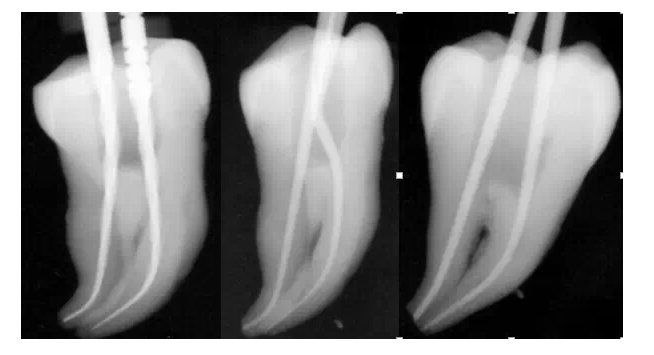

很意外吧,其實(shí)就是這么簡(jiǎn)單,第二步,一支鎳鈦銼,全程制備。以下是筆者用一支鎳鈦銼制備離體牙后試主尖的X-ray影像。

彎曲根管制備——ONE FILE FLEX共兩步,同樣是這么簡(jiǎn)單。ONE FILE FLEX X-ray片實(shí)拍得悅 ONE FILE FLEX的使用參數(shù):轉(zhuǎn)速:450轉(zhuǎn)/分 扭矩:1.0-2.0